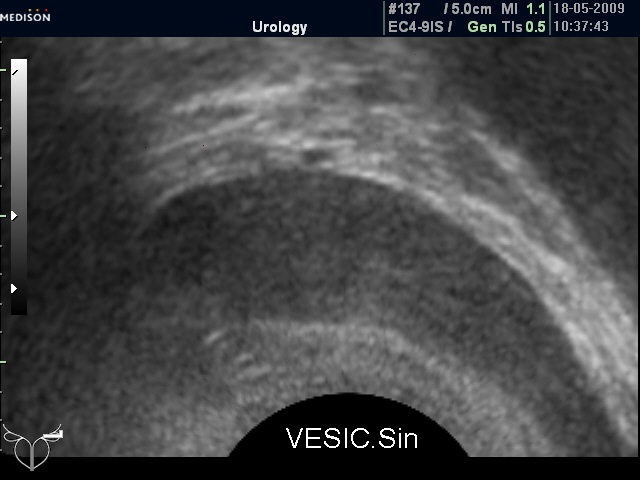

Досылаю фото семенных пузырьков.

Хронический везикулит